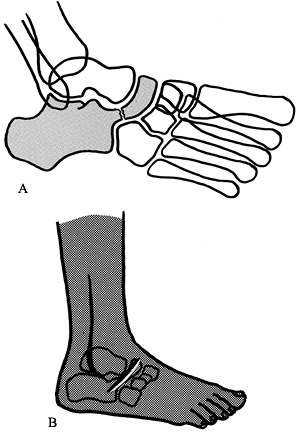

convex pes valgus, is a complex, rare, foot deformity that is resistant

to conservative treatment. There is a continuum from a relatively mild,

flexible form (oblique talus) to a rigid, severe deformity

characterized by a plantar-flexed talus, hindfoot equinus, and dorsal

dislocations of the talonavicular and calcaneocuboid joints. The heel

is always in rigid valgus. There are contractures of the Achilles

tendon, peroneus tertius, long-toe extensors, and tibialis anterior

muscle (Fig. 167.18). Lateral roentgenographs

taken in full dorsi- and plantarflexion differentiate the more flexible

oblique talus from the severe variety; oblique talus exhibits severe

deformity in dorsiflexion but a relatively normal relation between the

talus and calcaneus in full plantar flexion (16).

![]() |

|

Figure 167.18. Contractures involved in severe congenital vertical talus.